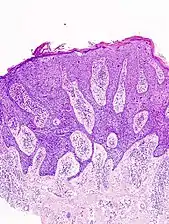

Bowen's disease is essentially equivalent to and used interchangeably with SCC in situ, when not having invaded through the basement membrane.[33] Depending on source, it is classified as precancerous[34] or SCC in situ (technically cancerous but non-invasive).[35][36] In SCC in situ (Bowen's disease), atypical squamous cells proliferate through the whole thickness of the epidermis.[33] The entire tumor is confined to the epidermis and does not invade into the dermis.[33] The cells are often highly atypical under the microscope, and may in fact look more unusual than the cells of some invasive squamous cell carcinomas.[33]

SCC in situ